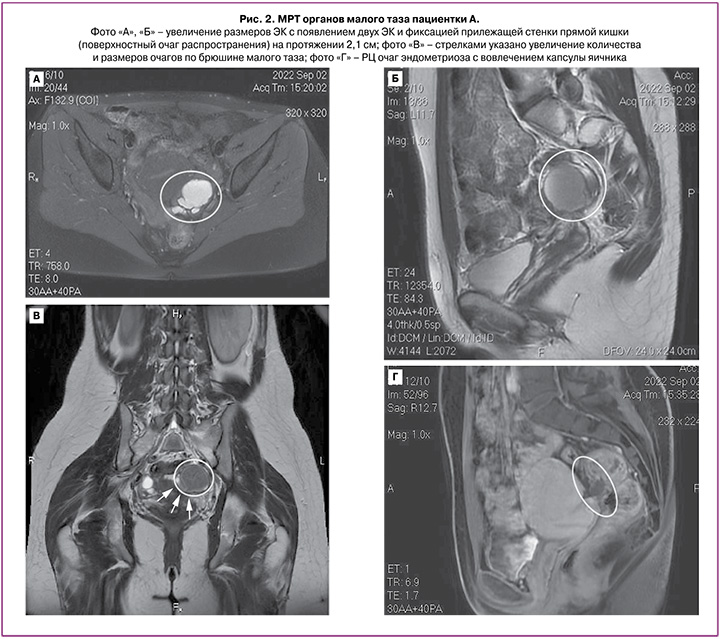

При МРТ органов малого таза с контрастированием (02.09.2022 г.) отмечается массивный РЦ очаг (2,8×1,2×3,1 см) (рис. 2) эндометриоза с преимущественным распространением в левые отделы, вовлечением левого яичника и стенки прямой кишки, без признаков глубокого прорастания, ЭК левого яичника (4,1×3,9×3,4 см; 2,3×1,0×1,4 см; 0,8×0,5 см), МР-признаки эндометриоидных гетеротопий по брюшине таза и КМС на фоне спаечного процесса. МР-признаки аденомиоза.

Таким образом, РЦ очаг эндометриоза почти за 2 года увеличился более чем на 90% от исходного значения (исходно – 1,7×0,8×0,6 см; через 2 года – 2,8×1,2×3,1 см). Увеличились размеры ЭК левого яичника до 4,1×3,9×3,4 см (ранее – 1,2×0,5×0,9 см) с появлением двух ЭК (размерами 2,3×1,0×1,4 см; 0,8×0,5 см), с фиксацией прилежащей стенки прямой кишки (поверхностный очаг распространения) на протяжении 2,1 см; также увеличились количество и размеры очагов по брюшине малого таза.